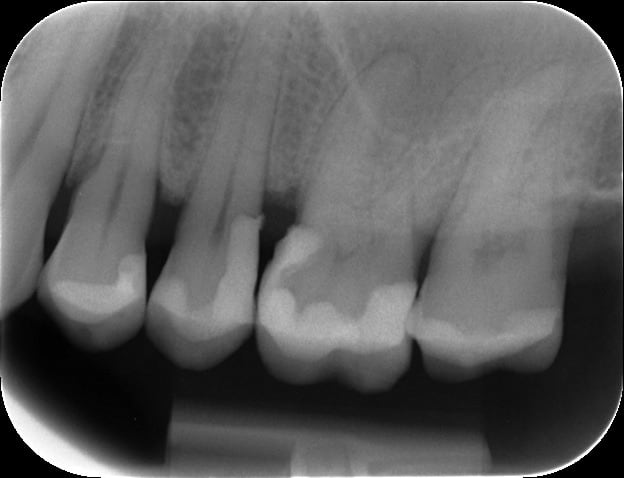

Bon voilà la radio "post-op"!...après deux rendez-vous de 90 minutes et pas mal de peine!

Fil de rétraction en place, pose de la digue, matrice Tofflemire à bosse...et j'ai réussi à obtenir quelque chose d'étenche et de sec. Du coup deux composites et pas de CVI. Et restauration d'un bon point de contact.

Le patient est au courant qu'il faudra surveiller les dents de près, et faire à chaque contrôle des test de vitalité.

Le travail est sûrement criticable, j'attends donc des remarques, mais pour une première perso je suis plutôt satisfait d'avoir éviter extraction et implants!

Sur la molaire, je ne sais pas pourquoi le composite fait cette vague car j'ai passé des disques et une bande de strip à polir...